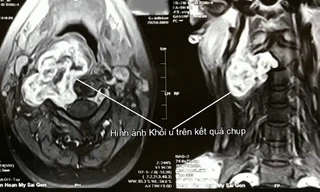

Ung thư thanh quản có những triệu chứng giống với cảm cúm nên có thể bị nhầm lẫn. Nam giới bị bệnh này nhiều hơn nữ giới, đặc biệt những người uống bia rượu nhiều.

Thanh quản là cơ quan tạo âm trong quá trình phát âm, rối loạn giọng là dấu hiệu thường gặp nhất khi có bệnh lý ở thanh quản biểu hiện bằng khàn tiếng ở các mức độ khác nhau từ nhẹ đến nặng.